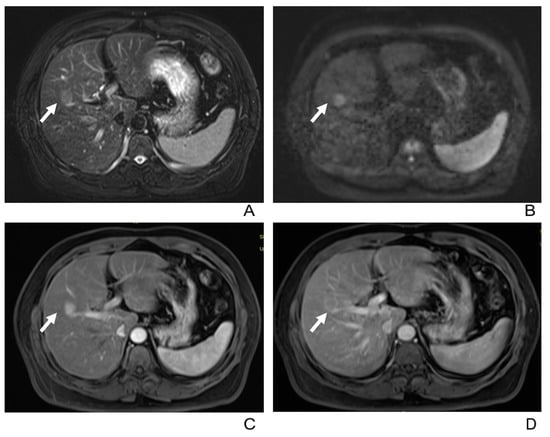

- Four patients had portal vein tumor thrombosis (Figure 3).

- Three patients exhibited intrahepatic biliary dilation, and one patient had distal metastasis on the 12th rib (Figure 3).

| Venous tumor thrombus | 4/38(11%) |

| Biliary dilatation | 3/38(8%) |